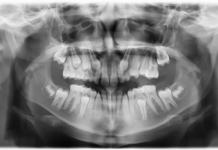

Il paziente era stato prima inviato a un chirurgo orale per un innesto osseo al fine di aumentare il volume osseo inadeguato che impediva il posizionamento degli impianti. Come sito donatore è stata scelta la cresta iliaca, ma questa procedura chirurgica aveva portato a un minimo incremento della quantità di osso disponibile. Invece di operare una seconda volta per incrementare il volume osseo prima dell’inserimento degli impianti, il clinico ha deciso di richiedere una TC per una valutazione più accurata. Prima della TC è stata realizzata una protesi in cera. In questo modo, i clinici coinvolti nelle procedure chirurgiche e protesiche erano consci di dove sarebbe stato necessario posizionare i denti artificiali al fine di ottenere un risultato estetico soddisfacente (figura 1). È stata quindi realizzata una protesi radiografica dal duplicato della protesi in cera da far indossare al paziente durante la scansione TC. Per la protesi definitiva si è optato per una Toronto. La TC scan/protesi radiografica facilitano notevolmente il piano di trattamento per quanto riguarda la determinazione del numero e della posizione degli impianti prima della chirurgia.